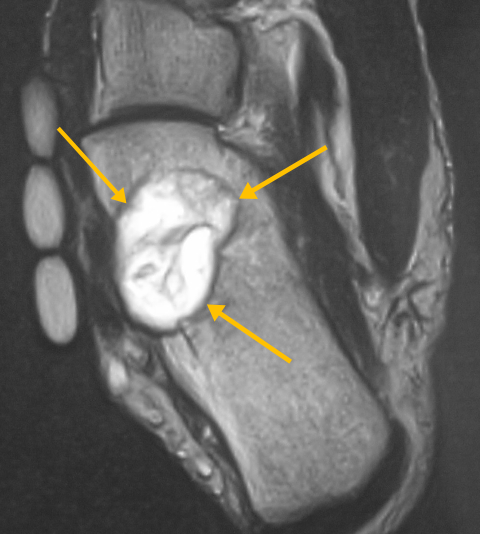

Radiographic imaging is used to help form a diagnosis of CMF. These include, X-Ray, MRI, CT and Bone Scans. An example of a CMF MRI is shown.